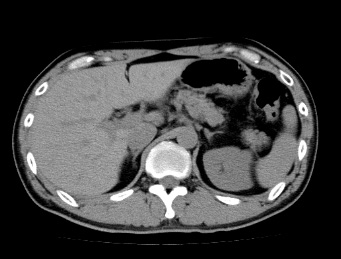

CT検査はエックス線を使用し、体の断面(輪切り状)を撮影するものです。

撮影部位は全身が対象で、造影剤を使用しない単純検査と造影剤を使用する造影検査があります。撮影時、CT装置の中を通過しますが、圧迫感は少なく撮影は短時間です。

単純検査

造影剤を使用しない検査で、臓器や骨、筋肉など、その形や状態を画像化します。主に、造影剤を使用しないでも診断ができる疾患や、造影剤を使用すると診断が困難になる疾患に対して行われます。